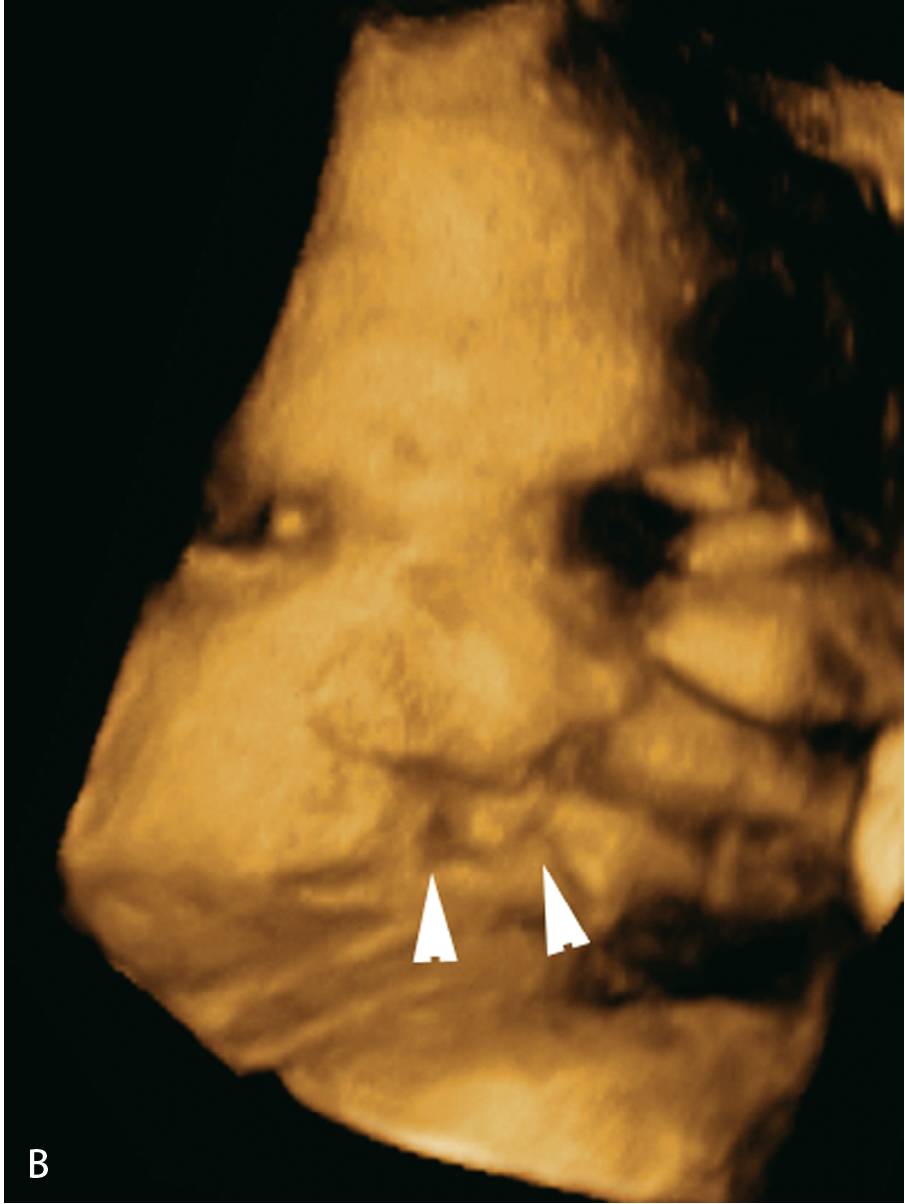

1.3双侧唇裂.(b)同一胎儿的三维图像显示双侧唇裂(三角箭头).图6.1.

胎儿双侧唇裂四维成像图